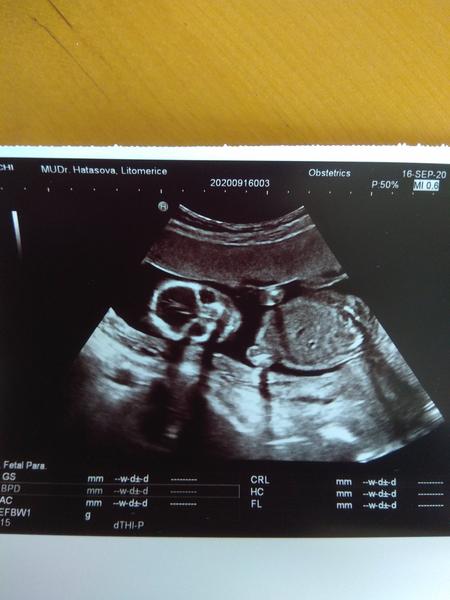

@rennye pan doktor rekl, ze nejspis kluk podle screeningu ve 13 tt😄ale uvidime!😃

@rennye takze nakonec je to kluk 😄💙